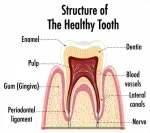

На мой взгляд, есть непролеченный участок в канале. Думаю, это он воспалился и симптомы очень сильно похожи на периодонтит.

Возможно, имеет смысл перелечить каналы зуба, а также заменить штифт на штифтовую вкладку + коронка.

Возможно, боли связаны с ошибками во время лечения каналов, что могло привести к периодонтиту.